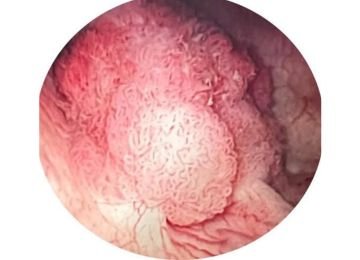

Uro-oncology

Uro-oncology is a specialized branch of medicine that deals with the diagnosis and treatment of urological cancer like Kidney cancer, ureteric cancer, prostate cancer, bladder cancer, testicular cancer and penile cancers.